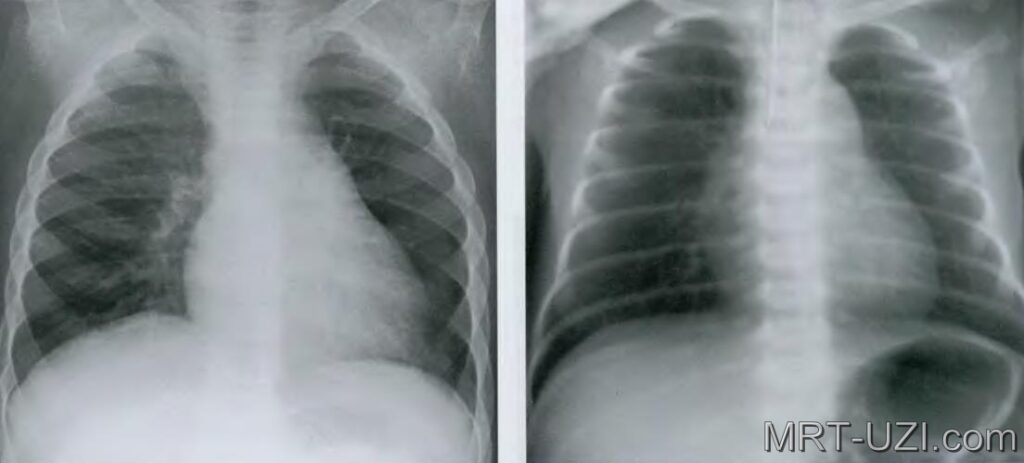

Фото 44 — Рентген легких в двух проекциях